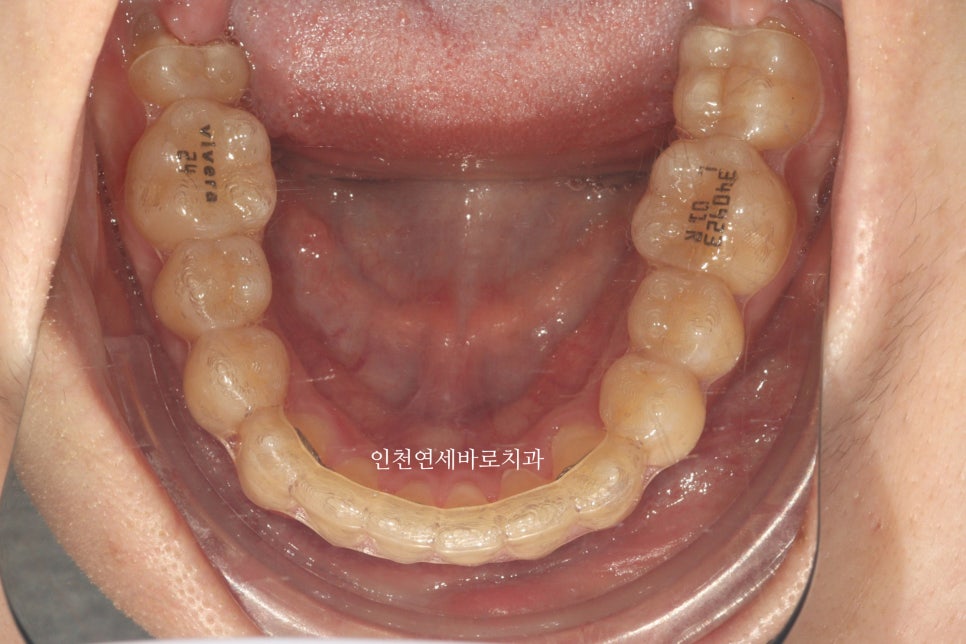

그리고 비베라까지 제작했습니다.

#비베라 유지장치가 여러가지 유지장치들에 비해 갖는 장점은 특별하진 않을 수 있습니다.

가장 중요한 핵심 가치인 '유지' 라는 측면에서는 모든 장치가 똑같은 역할을 합니다.

하지만 기계로 만들기때문에 '정밀도' 라는 측면에서는 비베라가 좋긴 한듯 합니다.

하지만 저도 모든 환자분들께 #비베라 가 좋으니 #비베라 하세요 라고 추천하진 않아요

각각의 장단점이 있기 때문에, 환자분이 들어보고 결정하시면 됩니다.

비베라는 제작 기간만 약 20일쯤 걸려요

진짜 빨리오면 2주정도에 도착하는데 여유롭게 3주로 예약을 잡아드리고 있습니다.